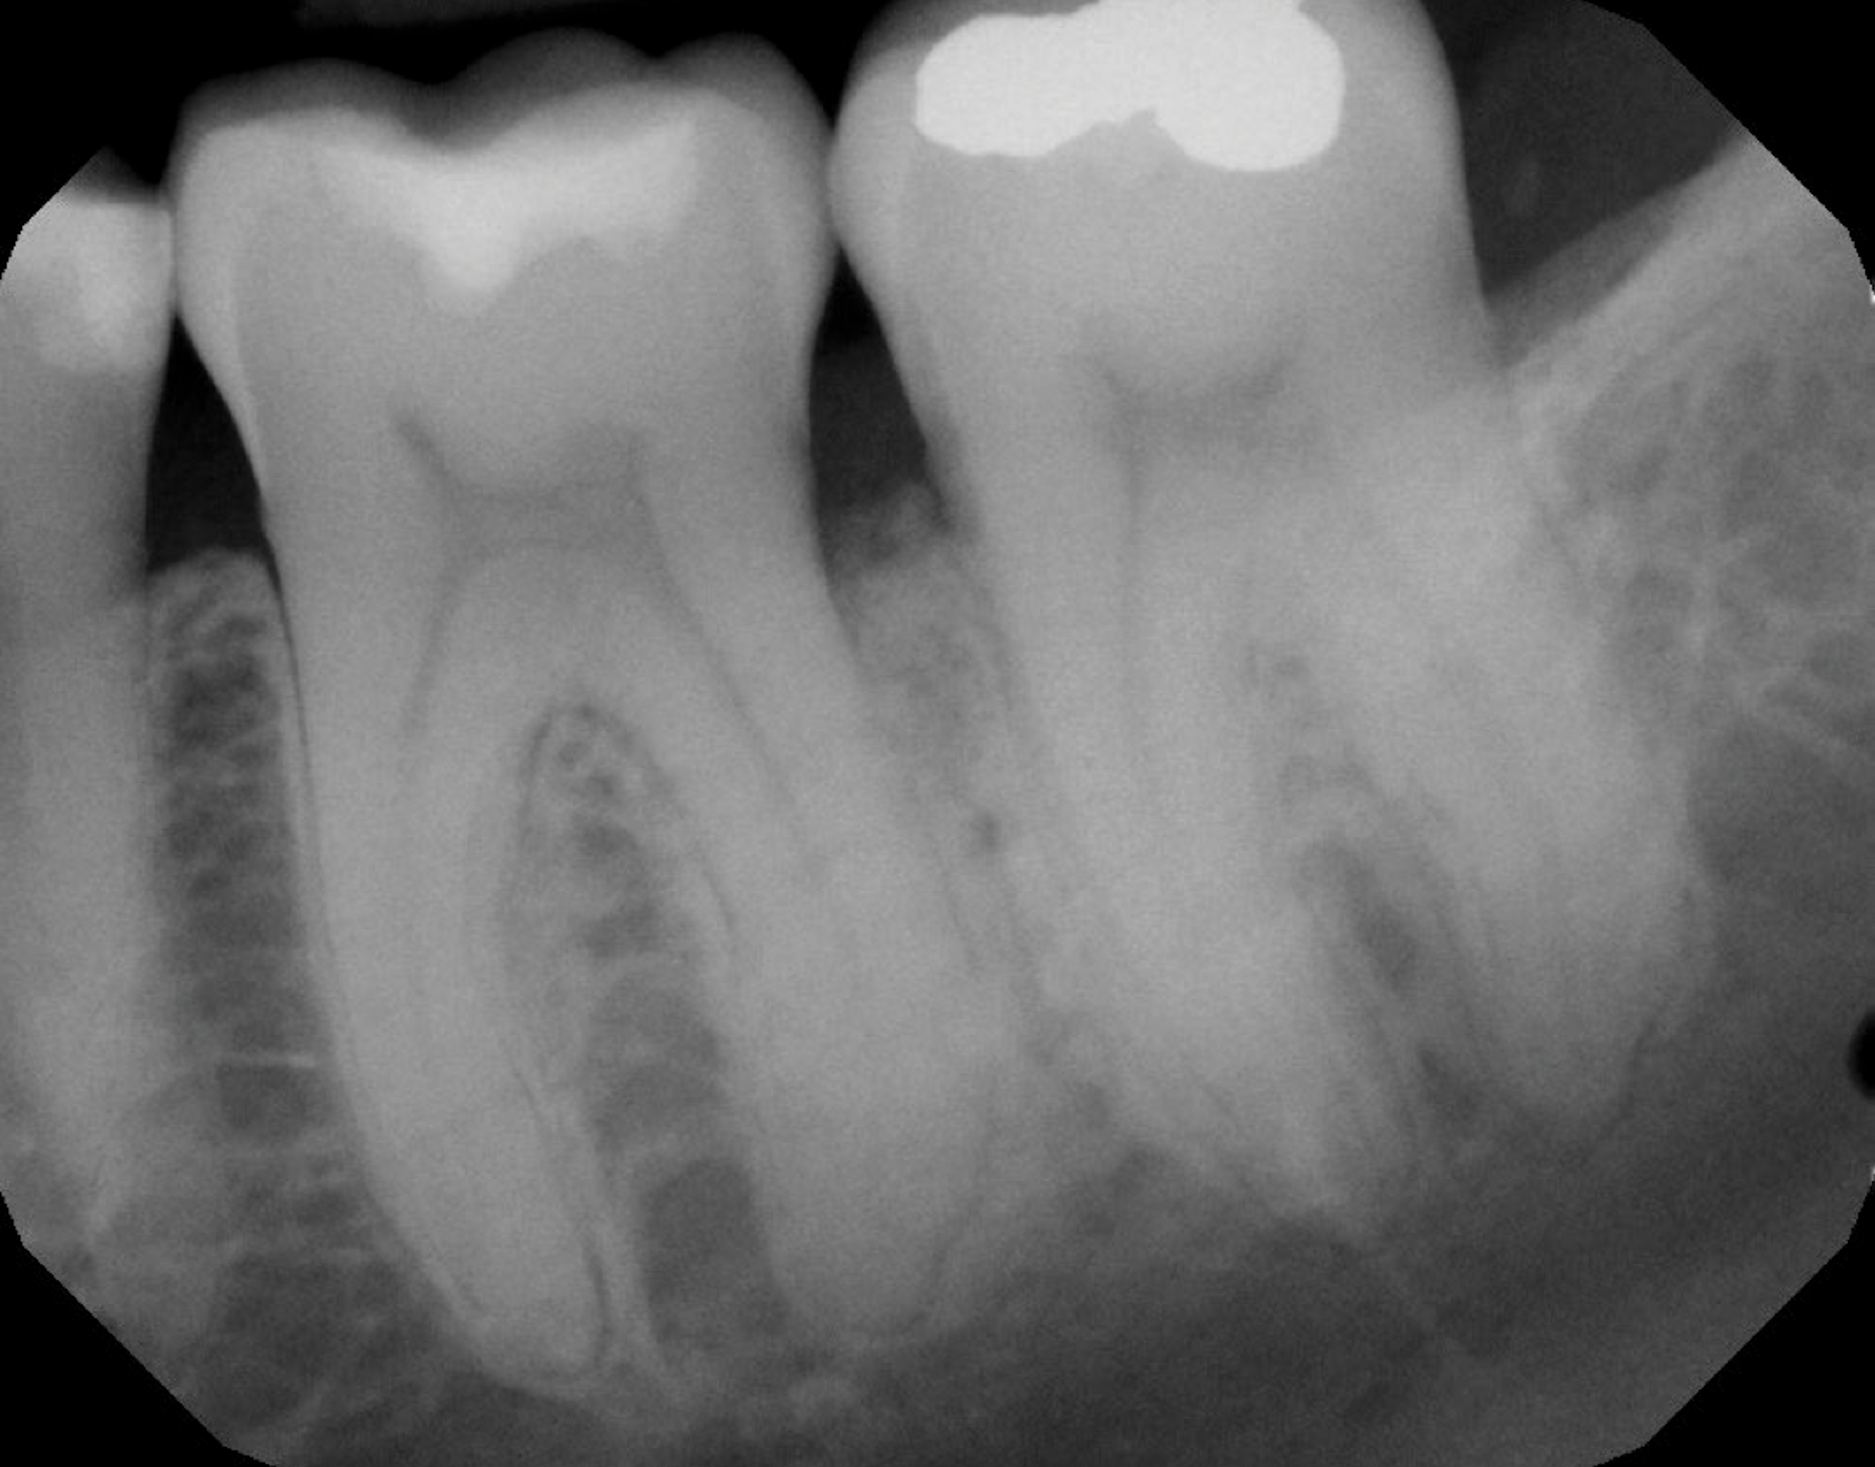

Fig 1. Tooth No. 19 at presentation, buccal view.

Figure 1

In the case presented, a 56-year-old healthy nonsmoking male patient, diagnosed with periodontitis stage III, localized, grade B, had been under care in a private practice periodontal office (RAL) for 25 years. He had a history of good compliance with his treatment (full-mouth plaque score <20%). During the COVID-19 pandemic, the patient missed three supportive periodontal therapy (SPT) visits over a year, resulting in periodontal breakdown interproximal between teeth Nos. 18 and 19 (mandibular left second and first molars, respectively). At his most recent periodontal maintenance visit, significantly increased periodontal probing depths of up to 10 mm with bleeding on probing were noted (Figure 1 through Figure 3). The periapical radiograph revealed a deep, narrow three-wall intrabony defect at the distal aspect of tooth No. 19, with class I buccal furcation involvement (Figure 4). According to the periodontal risk score (PRS),15 formerly known as the Miller-McEntire periodontal prognosis index, the tooth prognosis at the patient's initial examination was "good" (score = 5), taking into account that he was unaware of his hemoglobin A1C (HbA1c) levels. This scoring motivated the patient to be tested, and his follow-up HbA1c was <6%, thus reducing his PRS to 3, which was considered "excellent," as the PRS target goal for regenerative procedures is a score of <5.15

Tooth No. 19 presented with no mobility and tested vital endodontically. Soft-tissue anatomy was intact, with a keratinized tissue width of >2 mm. The operator was experienced, with no environmental stress and used checklists. Thus, based on the presurgical risk assessment, the patient presented a low-medium risk for periodontal regenerative therapy (Table 2).